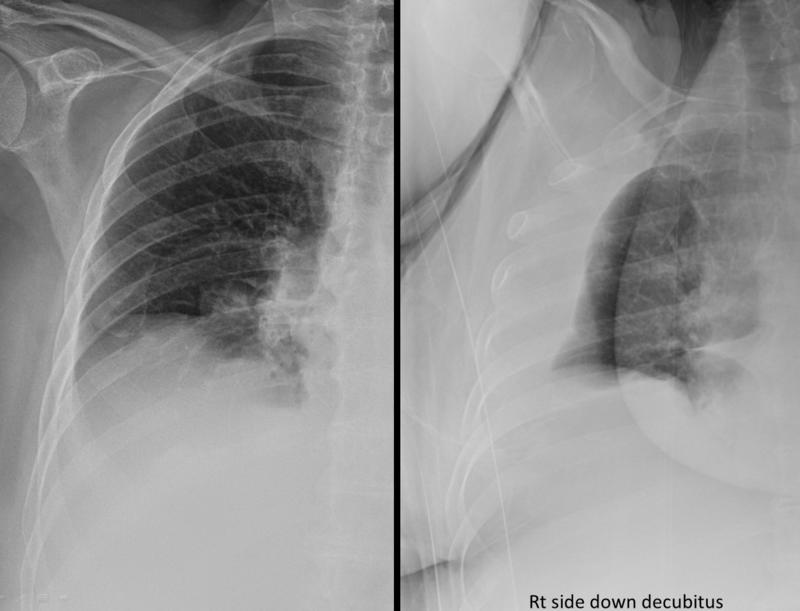

Gallery Pleural Subpulmonic effusion

Subpulmonic effusion